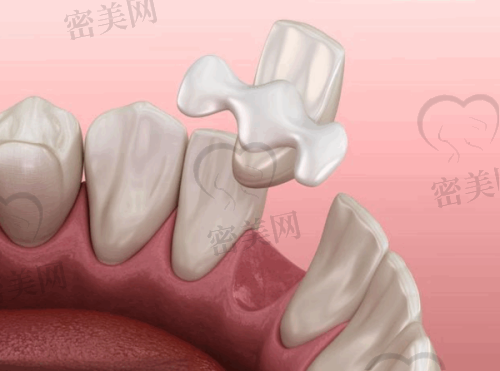

5. 美学修复:开展全瓷冠修复、瓷贴面、3M纳米树脂补牙等项目。美学修复不仅能够修复牙齿的缺损和损伤,还能改善牙齿的外观,让患者拥有更加自信的笑容。全瓷冠修复具有美观、耐用等优点;瓷贴面则可以在不损伤牙齿的前提下,快速改善牙齿的颜色和形状;3M纳米树脂补牙则能够与牙齿理想融合,修复牙齿的正常功能和美观。